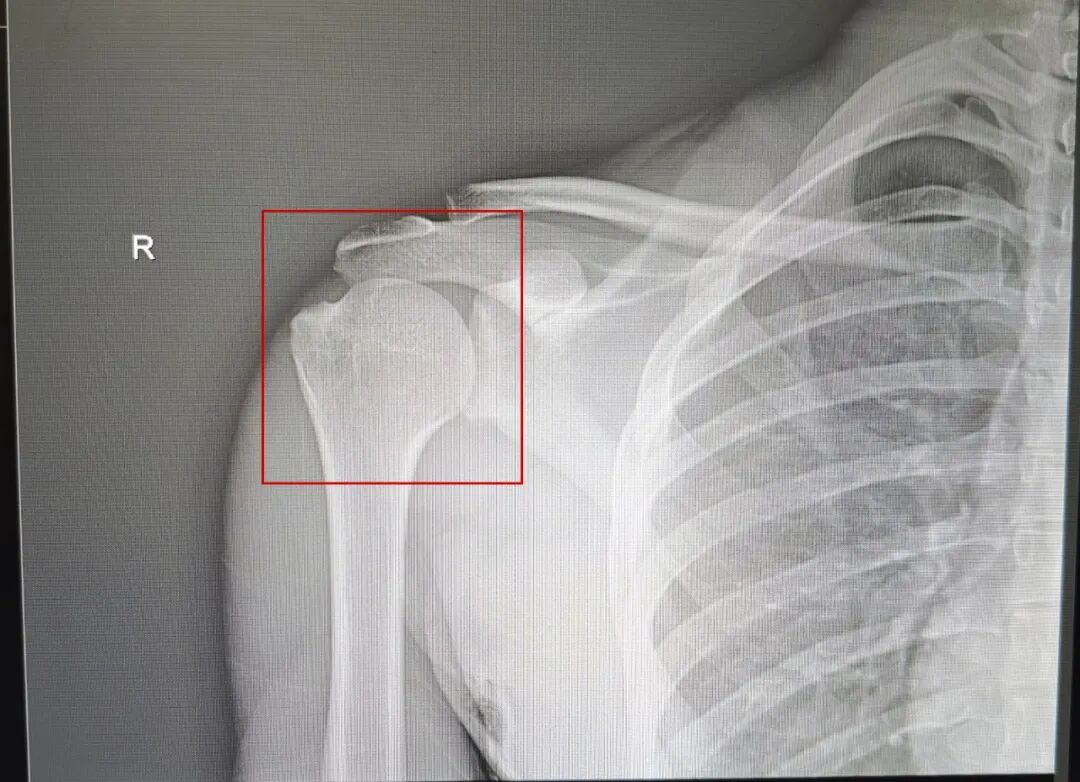

DR显示:脱臼的右肩关节成功复位